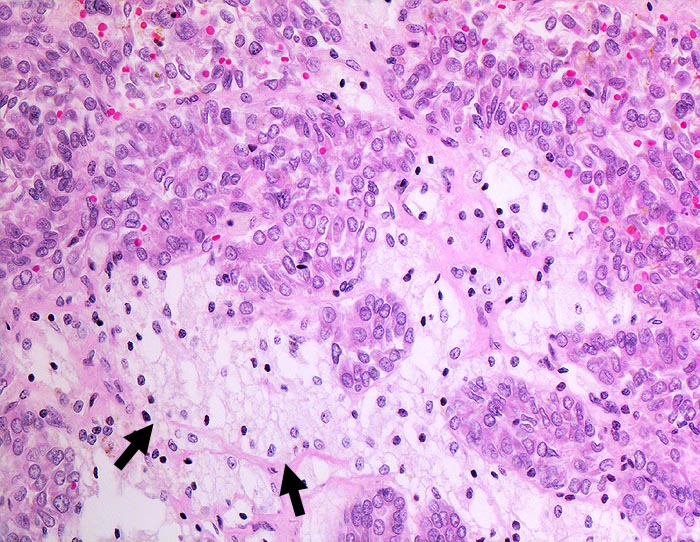

PathoPic – image database / PathoPic ID 1269 - Papilläres Nierenzellkarzinom basophiler Typ 1

Papilläres Nierenzellkarzinom basophiler Typ 1

Kleine basophile trabekulär (an anderer Stelle papillär) angeordnete Tumorzellen. Kleine ovale Kerne mit feinen Nukleolen. Charakteristische Ansammlung von Schaumzellen im Stroma.

7cm grosser Tumor ohne Durchbruch der Nierenkapsel, ohne Einbruch ins Nierenbecken.

Basophile und eosinophile papilläre Nierenzellkarzinome zeigen unterschiedliche genetische Veränderungen. Der basophile Typ hat eine bessere Prognose als der eosinophile allerdings in der multivariaten Analyse nicht signifikant. Eosinophile Tumoren sind meist höhergradig (2-3) als basophile (1-2).